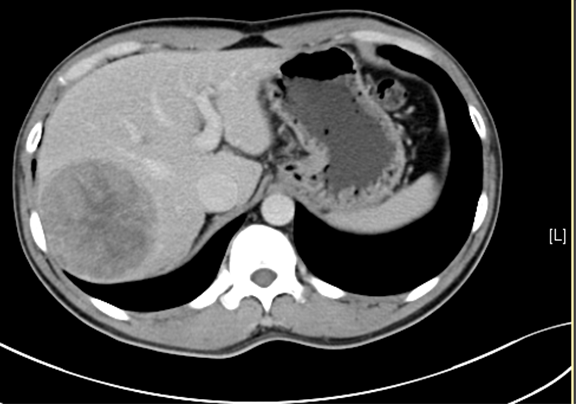

术前CT检查:

动脉期

静脉期

平衡期

下腹部增强CT示:肝右后叶占位性病变,考虑肝癌可能性大。

通过调节窗宽窗位调整CT序号,对肿瘤,肝实质,胆囊,下腔静脉,肿瘤,肝动脉、门静脉及肝静脉等进行三维重建;系统自动计算肿瘤体积和肝脏体积。

模拟手术操作,自动计算切除肿瘤体积。肝脏体积为1197ml,肿瘤体积为262.5ml,肿瘤体积为肝脏体积的21.9%,通过比对30-40岁正常肝脏体积为1323.35±298.47ml,通过术前模拟手术,精准判断切除后剩余肝脏体积能耐受,避免肝衰竭发生。